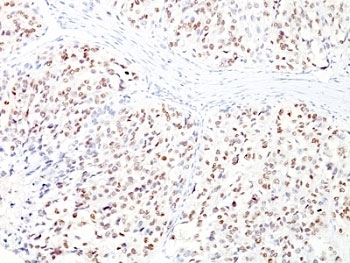

IHC: Formalin-fixed, paraffin-embedded human melanoma stained with MITF antibody cocktail (clones D5 + MITF/915).

Applications Immunohistochemistry (FFPE) : 1-2ug/ml for 30 min at RT